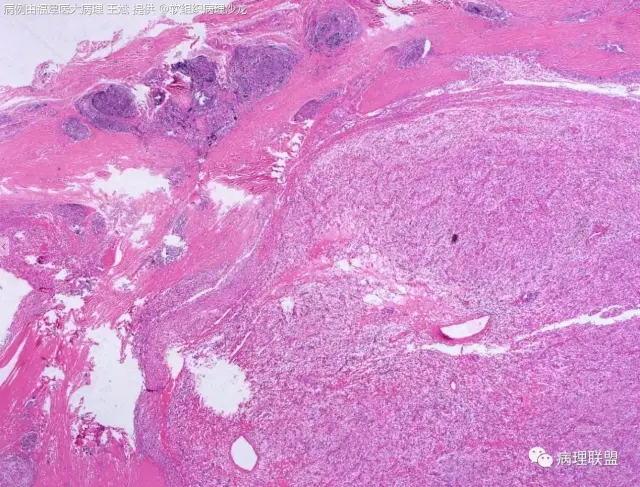

38岁,女性,手部小指背侧皮下肿物,3×2cm(病例由福建医大病理 王斌提供,致谢!)

血管瘤样纤维组织细胞瘤的肿瘤周围有淋巴细胞鞘,结节状分布,有假包膜,出血囊性变的为其主要特点,当然少数病例可以没有出血囊性变却出现粘液变。肿瘤细胞有一定异形性,属于低度恶性或交界性,最好做个FISH,看看有没有EWSR1-CREB1融合基因,刚查了一下,血管瘤样纤维组织细胞瘤还有另一种EWSR1-ATF1融合基因,无论是哪种,用EWSR1分离探针就可以检测